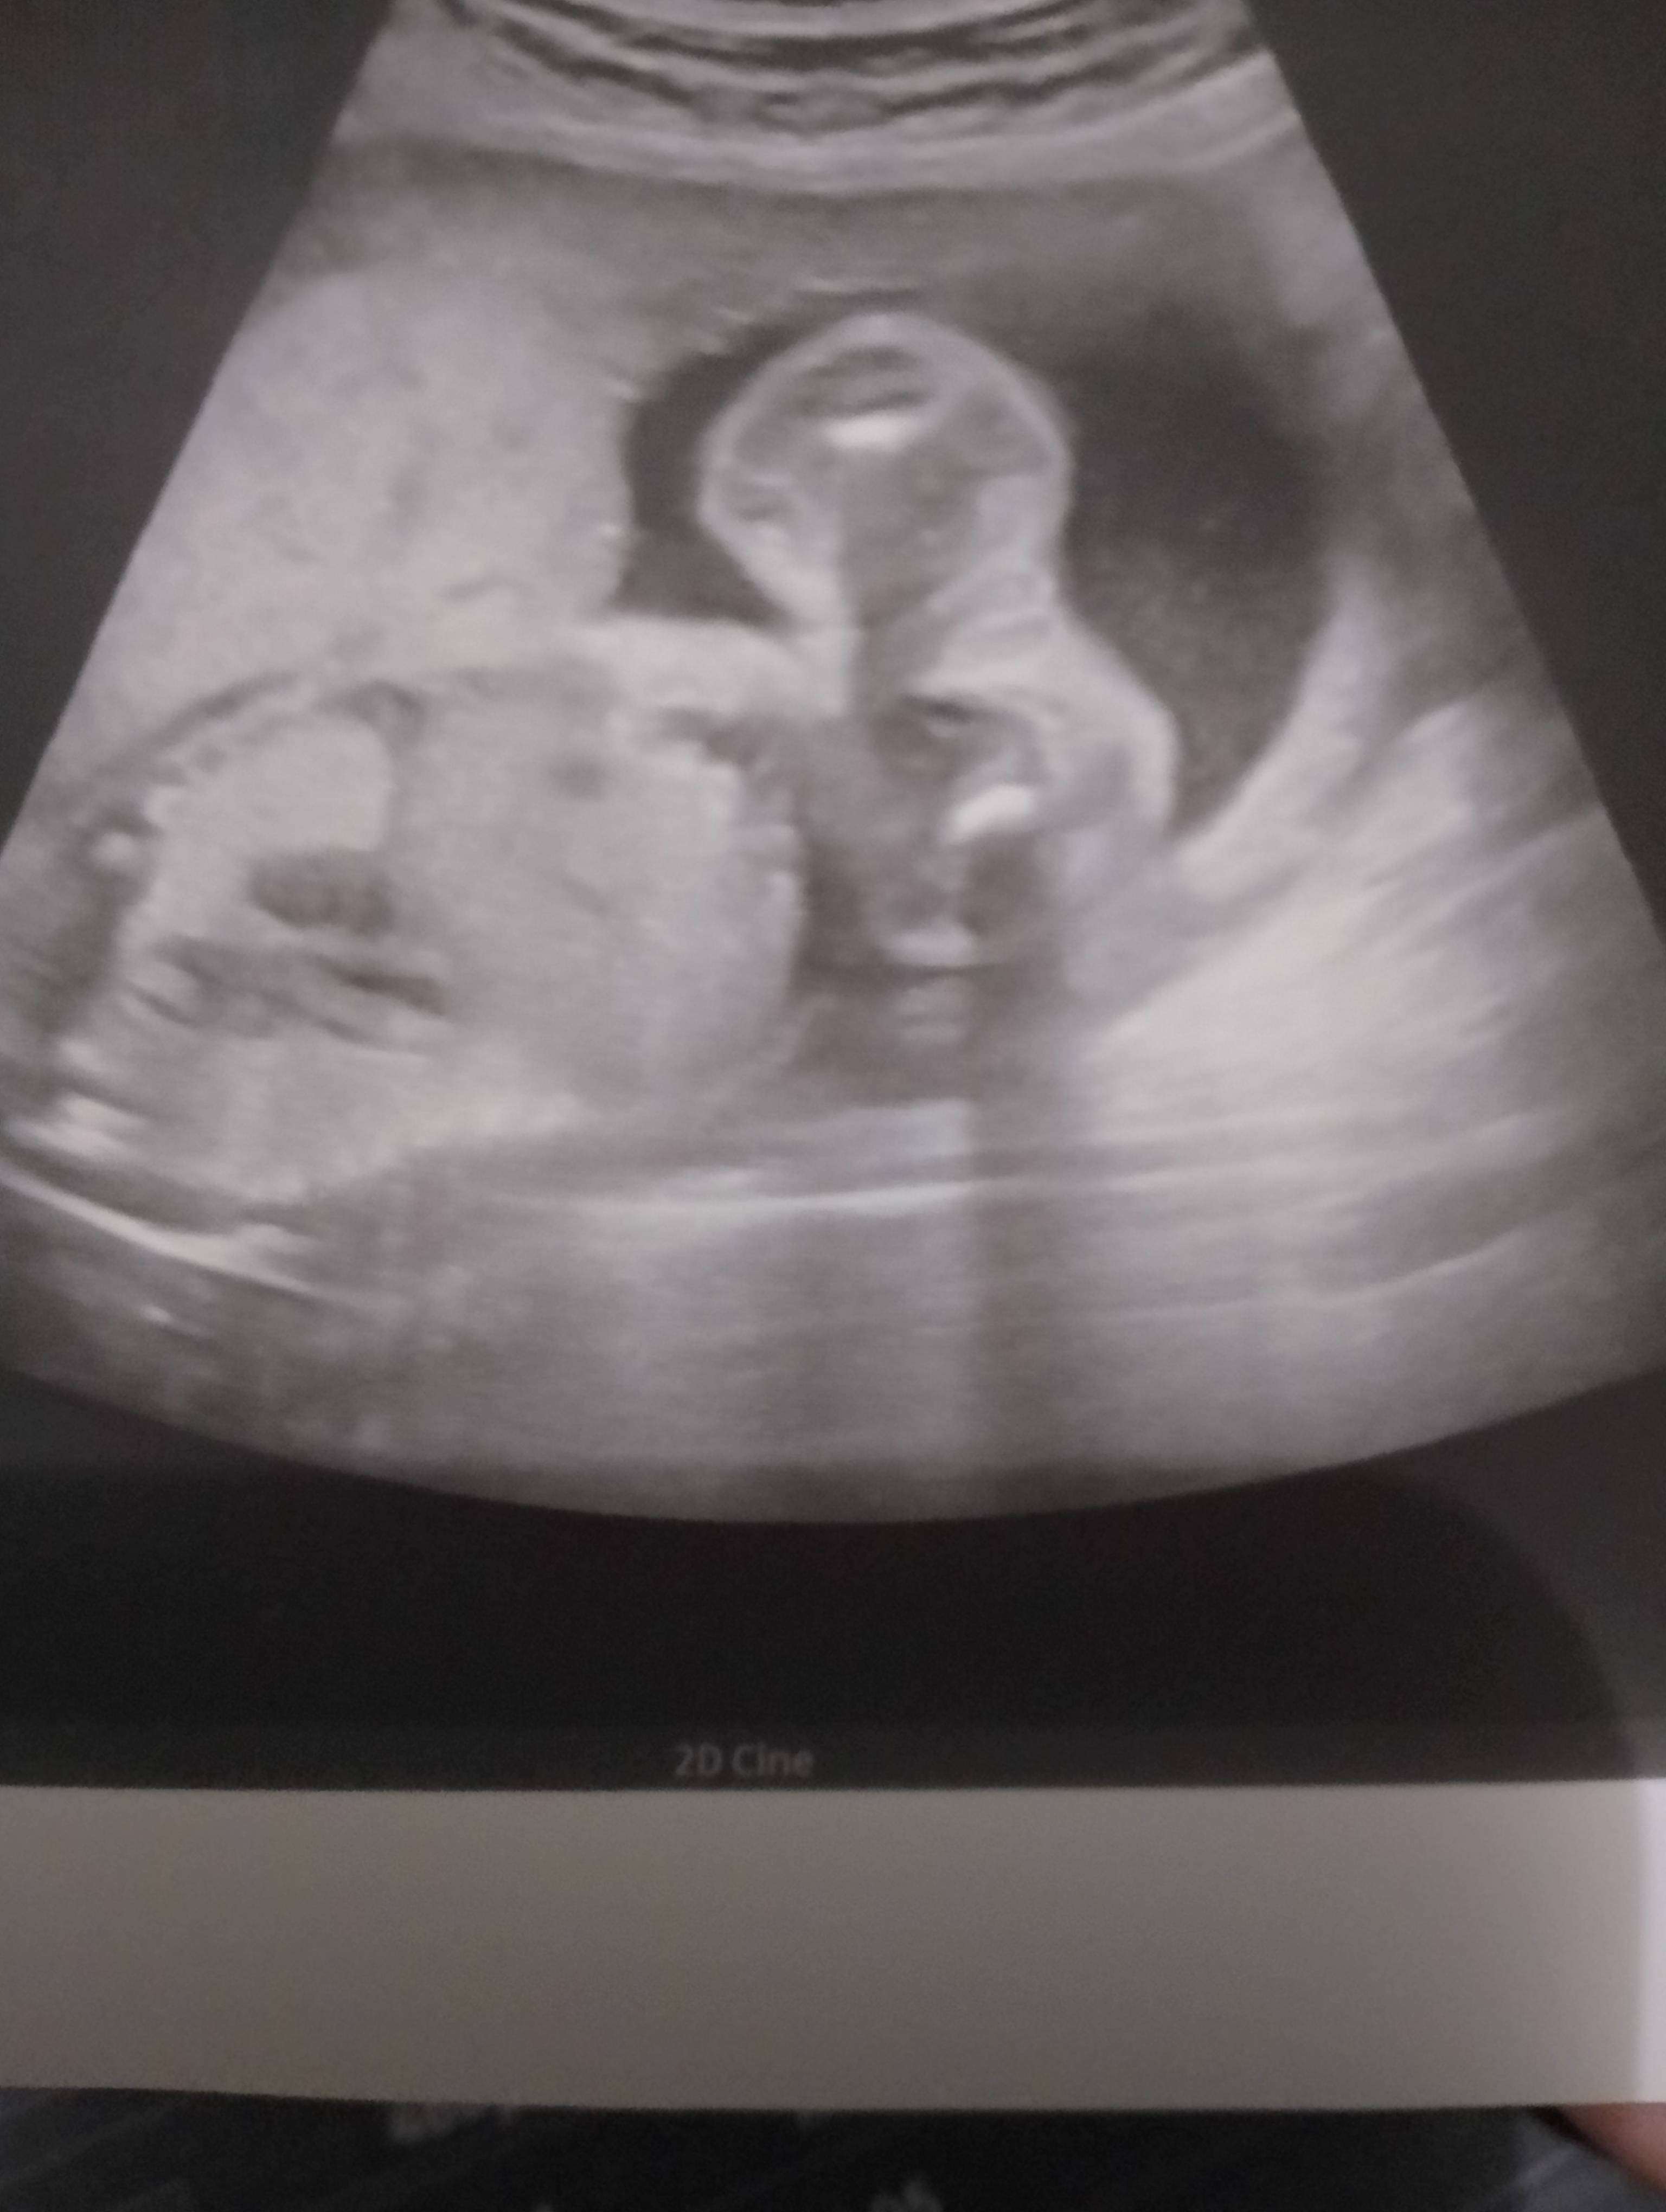

U mnie w tym tygodniu też mówił że chłopaczek bo widział siusiaka więc może być tak jak mówisz z tym przerośnieciem bo teraz jak byłam w 19tc widział dziewczynkę 🫣 Czekamy na połówkowe 30.01 może się potwierdzi 🥰

Tu to Ewidentnie jest dziewczynka :) tyle co ja już tych zdjęć przejrzałam. Widać odrazu